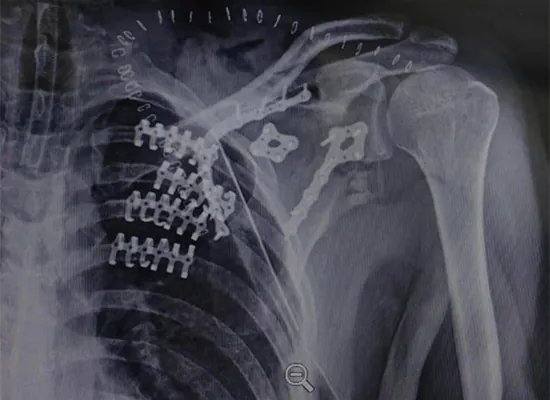

Ja min bɛ kɛ ka kɔn opereli ɲɛ, o y’a jira ko kɔkili karilenw bɔra u nɔ na minnu bɛ sɔrɔ disi kogo basigibaliya la, ka fara claviculaire sen donli kan. Ni an y’a jateminɛ ko kolotugudaw tiɲɛni hakɛ ani ko fiɲɛ bilali farati la, opereli sabatili sugandira. O kɛcogo in kɛra ka ɲɛ dɔgɔtɔrɔ Israel Eduardo fɛ, a laɲini ye ka barajuru labɛnni segin a cogo kɔrɔ la, ka ninakilidegun kɛcogo ɲɛ, ani ka fixation sabatilen di walasa ka baara kɛ joona.

Radiographie de radiographie (radiographie) jateminɛ ye rib rib fractures (rib kari) caman jira ni taamasiɲɛw ye minnu bɛ bɛn disi kogo basigibaliya ma. Rib tɛmɛsira tiɲɛni y’a jira ko barajuru lamagacogo tɛ kelen ye, o bɛ dɔ fara ninakiliko gɛlɛya kan.

Opereli kɛcogo tun sinsinnen bɛ disi kogo sabatili seginni kan ni sɔgɔsɔgɔninjɛ ni kɔkili yɔrɔw kɔnɔna sirili ye, o faralen ɲɔgɔn kan ni a ni a ɲɔgɔnna claviculaire fractures sabatili ye ni a jirala.

Opereli kɔfɛ ja lajɛ ye kɔkili seginw jɔli sabati ani ka barajuru sinsinni segin a cogo kɔrɔ la. Thoracic cage ye sigida labɛncogo ɲuman jira ni dalilu si tɛ a la min b’a jira ko fɛn dontaw bɛ bɔ u nɔ na.

Opereli kɔlɔlɔw y’a jira ko disi kogo ka farikolo-ɲɛnajɛ-cogo kura segin-seginni ani a ka baarakɛcogo sabatili, o bɛ opereli disi kogo sabatili nafa jira nin joginda in na. Ja lajɛ sɛgɛsɛgɛli ni kɛnɛyako ɲɛnabɔli y’a jira ko fɛɛrɛ tigɛlen don.